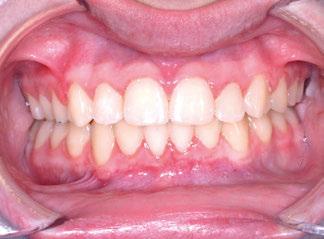

Figuras 1-3.

La niña de las figuras 1 a 3 presenta una leve asimetría facial con patrón braquifacial por tercio inferior disminuido y mentón desviado ligeramente hacia la derecha; los labios son competentes y en sonrisa apenas se exponen los incisivos. El perfil es excesivamente convexo,

La exploración intraoral (figuras 4 a 8) revela una Clase II molar y canina completa, líneas 1/2 dentarias superior 0,5 mm e inferior 1 mm ambas desviadas hacia la derecha, los incisivos superiores excesivamente protruidos y vestibulizados (seguramente debido a la interposición del labio inferior), resalte de 13 mm y sobremordida 2/3 de corona. La discrepancia oseodentaria

inferior es de -3,5 mm y la curva de Spee de 4 mm.